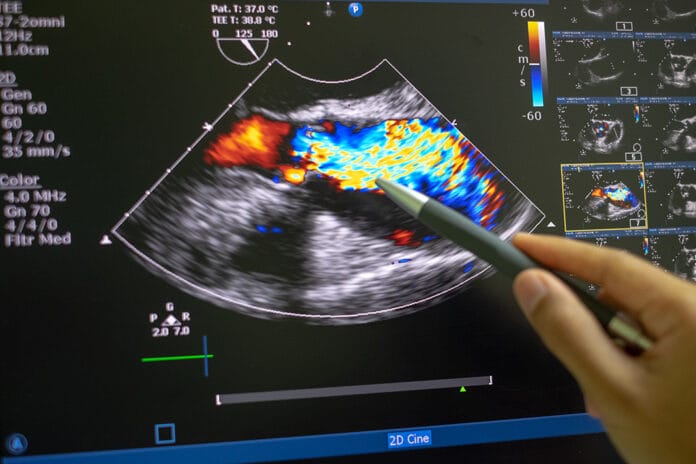

Potential Link of Periodontitis and Valvular Heart Disease Found

A retrospective study in Taiwan has revealed a potential link between periodontitis and the development of valvular heart disease. The results of the study...